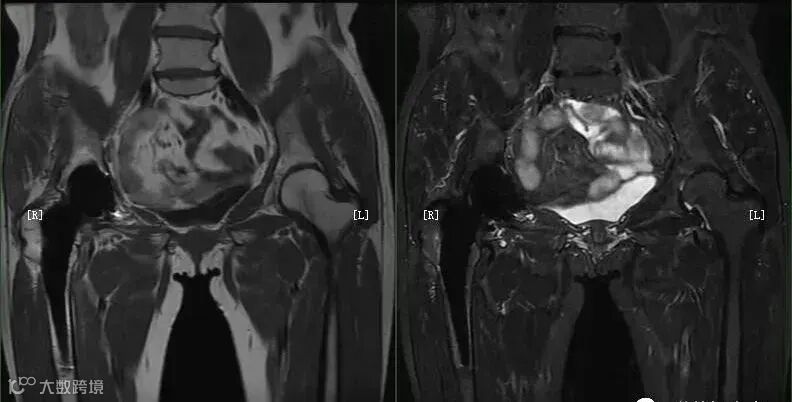

宽带宽+长回波链可使脂肪更亮,获得更优异的组织对比图像。如在盆底脏器的扫描中常使用该方式来突出对比。

在对有金属植入物的扫描中,采用高带宽可有效改善其磁敏感伪影导致的变形失真,如高带宽+STIR的方式。